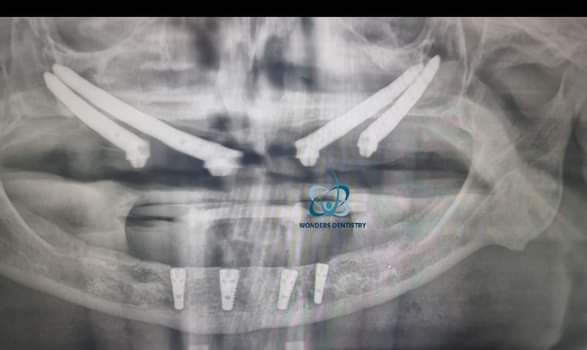

زيارتك الأولى يحدث فيها إجراء فحص شامل، مثل الأشعة السينية البانورامية و الاشعة ثلاثية الأبعاد لرؤية كمية العظام الموجودة في الفك، كما يقوم الطبيب بتقييم صحة الفم و بنية العظام.

زراعة الزيجوما هي زراعة أسنان مصممة خصيصا للمرضى الذين يعانون من فقدان شديد للعظام في الفك العلوي للحد الذي لا يسمح باجراء عملية زراعة تقليدية. على عكس الغرسات العادية، تكون الغرسات الوجنية أطول و يمكن ان يصل طولها من 30 ملم الى 55 ملم و يتم تثبيتها في عظام الخد ، و التي تسمى الوجنة. حيث تجنب الغرسات الوجنية من عملية ترقيع العظام او ما تسمى بزرع العظام و تجنب ايضا من عملية رفع الجيوب الأنفية، مما يقلل من عدد العمليات الجراحية و توغلها التي يحتاجها المريض اذا قام باختيار هذه الحلول الاخرى.

تعتبر الغرسات الوجنية أطول بكثير من الغرسات التقليدية حيث يتراوح طولها من 30 إلى 55 ملم تقريبا و يعد هذا الطول الممتد ضروري للوصول إلى العظم الوجني و تأمين استقرار الزرعة فيه، يسمح الطول المتزايد للزرعة بالتثبيت بقوة في العظم الوجني القوي، مما يوفر الدعم اللازم لتركيبة الأسنان فيما بعد.